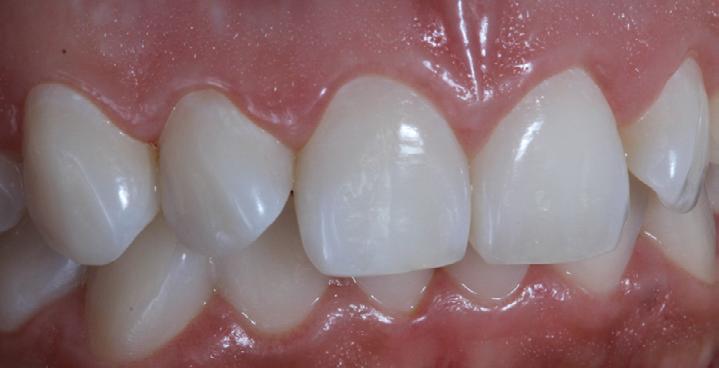

Reshaping of teeth and diastema closure with G-aenial A’CHORD. Courtesy of: Dr Andres Silva, Spain